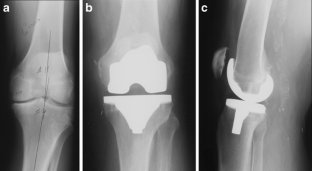

Fig. 1